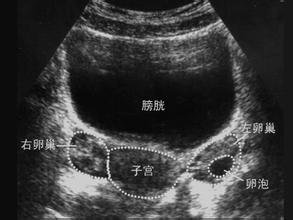

(1)B超监测排卵

生育期女性平均每月排出一个优势卵泡,受精能力约24小时,精子存活平均1-3天,所以最佳受孕期为排卵期前后2-3天。这样算来,我们就可以“打有准备的仗”了。

有的小伙伴就要问了,那排卵期该怎样监测呢?大致分以下两种,大家可以根据自身情况进行选择: